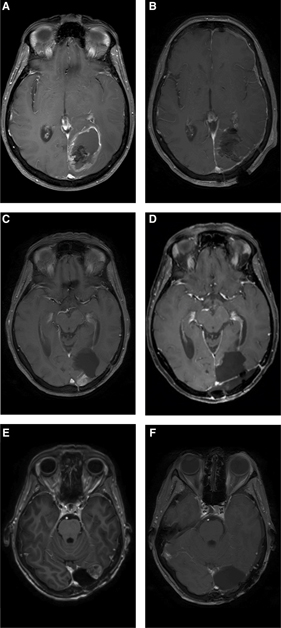

No randomized trials exist that randomize patients for surgery in the relapse setting, and most reported surgical series in recurrent GBM are retrospective (15). An overview of selected surgical outcome series is given in Table 1. Several authors have reported better outcome after surgery for recurrent GBM, compared to control nonsurgical populations. However, we have to take into account that these reports inherently suffer from selection bias, as patients who are selected for reoperation usually tend to be younger and have a better Karnofsky Performance Scale (KPS), and hence belong to a more favorable prognostic group (19). Azoulay et al. compared 68 reoperated patients with a matched cohort of nonsurgically treated recurrent GBM patients, based on initial extent of resection (EOR) and subventricular zone involvement (10). Median OS in the surgical subgroup was 9.6 months versus 5.3 months in the nonsurgical group, which was statistically significant. They concluded that reoperation, combined with additional rescue therapies, can induce prolonged survival in recurrent GBM. Chen et al. described 65 recurrent GBM patients, of whom 20 were reoperated. Median OS after recurrence in the surgical group was statistically higher with 13.5 months versus 5.8 months in the nonsurgical group (20). However, KPS at recurrence was also significantly higher in the surgical group, and 77.8% of the nonsurgical group received only palliative therapy. Tully et al. described 204 GBM patients of whom 24% were reoperated at recurrence, and they found a significantly improved survival of 20.1 months in reoperated patients compared to 9.0 months in recurrent patients who were treated nonsurgically (21). In their series, reoperated patients were younger, had a smaller initial tumor diameter, and were more likely to have an initial EOR of ≥50% at first resection. Moreover, reoperated patients had a significantly higher percentage of completion of adjuvant therapy (79.6% vs. 35.9%). To compensate for this selection bias, patients that were a priori unlikely to be selected for reoperation based on age or performance scale were excluded in a subgroup analysis. A much less significant, though still present, advantage for the surgical group was found at first recurrence, but not anymore at second recurrence. Moreover, reoperation was no longer an independent predictor of OS in a multivariate analysis. The authors suggested that the improved OS in the surgical group might be more of a reflection of favorable patient characteristics than surgery itself. Chaichana et al. showed a survival benefit resulting from repeat resections using a multivariate analysis and case control evaluation to correct for selection bias (22). In their series, median survival was 6.8 months for patients that had one resection versus 26.6 months for patients that underwent four resections. Very often, a more favorable course of disease and pattern of recurrence render these patients eligible for reoperation rather than vice versa (Figure 1).

Fig 1

Figure 1 A 57-year-old lady was diagnosed with a left occipital glioblastoma (A), for which a total resection was performed (B). She was treated with standard radiotherapy, temozolomide chemotherapy, and experimental dendritic cell vaccination. An asymptomatic recurrence in the medial wall of the resection cavity was seen in a routine follow-up scan 16 months after the first surgery (C). A second total resection was performed (D), after which combined CCNU and bevacizumab was given in the EORTC 26101 study. A second asymptomatic local recurrence at the lateral side of the resection cavity was seen 14 months later (E), and again a total resection was performed (F). Nine months later she developed a multifocal progression, resistant to temozolomide. She died 42 months after the first surgery.